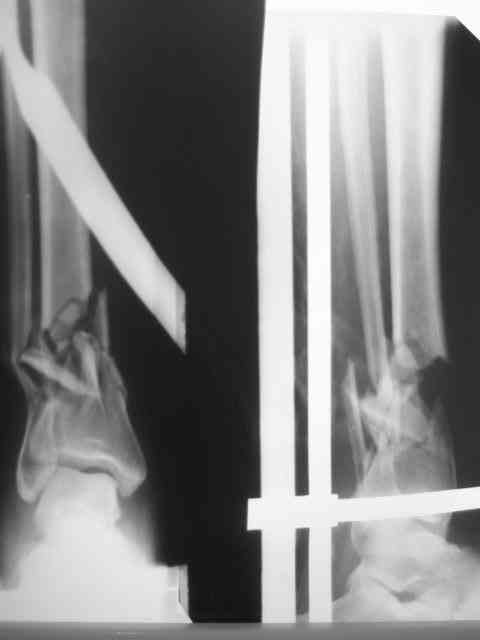

Из истории выяснилось: травма 29.01.07 Диагноз: Открытый оскольчатый перелом н/3 костей голени (якобы 2 Б Каплан), при поступлении операция из трех букв и скелетное вытяжение + остальная терапия. Затем выполнили остеосинтез штифтом (походу Эксперт стоит) видимо хотели зацепится за дистальный отломок, но скорей всего все было нестабильно и накинули этот сокращенный АВФ. На сегодня (162 дня): Больная ходит с ограниченной нагрузкой на конечность (трость). Движения в г/стопе качательные. Трофика мягких тканей не настораживает. Воспаления м/тканей нет.В планах: 1. удаление штифта 2.Наложение стандартного АВФ с фиксацией стопы и устранение всех смещений 3.Резекция нежизнеспособных костных отломков 4.Остеотомия в/3 большеберцовой кости с последующей дистракцией и замещением дефекта.Хотелось бы выслушать мнение по этому случаю!Возможен ли вариант если на опер.столе удастся устранить смещения одномоментной репозицией АВФ и не удалять штифт а производить транспорт большеберцовой кости на штифте? И стоит ли при таком коротком дистальном отломке пытаться блокировать в низу (имеется в виду в АВФ)Спасибо.

Пожалуй. Хотелось бы посмотреть на прицельный сниомк дистального отдела голени. Похоже, эпиметафиз смещен кпереди, и с гвоздем внутри это не исправить.

Не вижу необходимости в фиксации стопы. И дистальный отломок tibia достаточно велик, чтобы ввести в него 3-4 спицы с упорами. И голеностопный сустав уже давно пора мобилизовать, дальнейшая фиксация может кончится фиброзным анкилозом.